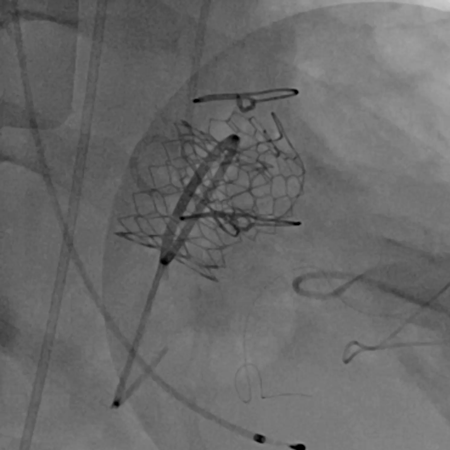

术后主动脉根部造影

术后左室造影

黄焕雷主任带领具有丰富经验的心脏麻醉医师、体外循环师、超声心动图医师、手术室、心外重症监护室、心脏导管室多学科团队,联合心内科专家谢年谨主任,为蔡先生实施小切口下、介入途径的主动脉瓣“瓣中瓣”、二尖瓣“环中瓣”的同期植入手术:黄主任首先在患者左前胸做一小切口,暴露患者的心尖,在跳动的心脏上“绣”上荷包作为介入导管、瓣膜的植入“门户”;随后,黄焕雷主任在超声心动图、放射透视的引导下,将一钢针在患者心尖“扎”入患者心脏内,为之后的瓣膜植入作为引导,具体来说就是将预先选择适合患者大小的生物瓣膜折叠、压缩入细长的输送管道内,好比将瓣膜这一“弹头”安放在输送导管这颗精准制导的“火箭”上,而黄主任的双手则控制这一精准发射和制导,再将瓣膜输送到主动脉合适的位置后释放,新的主动脉瓣便牢固地“卡”在了原有的主动脉瓣架内。经过透视和超声心动图评估,主动脉瓣位置合适,开放、闭合功能良好。随后,黄主任通过这一根钢针和输送导管,利用类似的方式,调整“火箭”的发射轨道,在原有二尖瓣人工瓣环内植入预先选择好大小的二尖瓣生物瓣膜,经过影像学方式评估,新植入的二尖瓣生物瓣工作良好。

黄主任带领的多学科团队,顺利地完成了国内首例“瓣中瓣”、“环中瓣”同期联合手术,现在蔡先生在术后两天,便顺利地从心外重症监护室转回了普通病房,经过不到两周的治疗,便康复出院了。原本重症、复杂的瓣膜疾病,在黄主任带领的多学科团队协作下,使用微创、介入的方式,为患者“量身定做”具体的治疗策略,改善原有手术效果、加速患者康复,让更多心脏病患者获得新生!